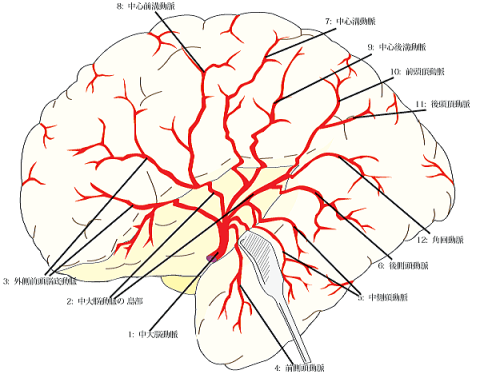

脳血管 #2-6 皮質枝動脈脳卒中リハビリテーション看護認定看護師の脳の中。

脳血管 #2-1 脳動脈と灌流域脳卒中リハビリテーション看護認定看護師の脳の中。

脳の動脈とその支配領域まっちゃんの理学療法ノート。